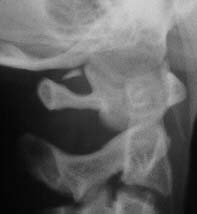

Spot Lateral